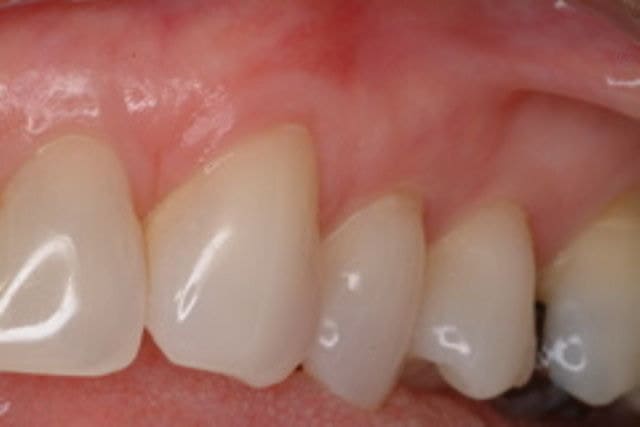

After

Patient: Jill